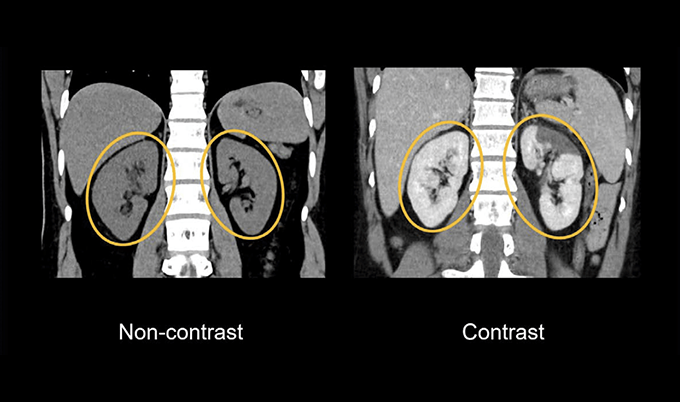

Picture this scenario. A radiologist examines a standard CT scan of your abdomen. They see your liver, but they can’t tell if that slightly darker area represents normal variation, scar tissue, or early-stage cancer. All three look remarkably similar on imaging without contrast.

Now inject iodine-based contrast material into your bloodstream. Within seconds, your blood vessels light up white on the scanner. Your kidneys process the contrast and highlight the urinary system. Any tumor present absorbs contrast differently than healthy tissue, creating clear boundaries that practically announce its presence.

Cancer detection and characterization depends heavily on contrast. Tumors develop their own blood supply to fuel growth. Contrast enhancement reveals this abnormal vascular pattern. A liver lesion might look identical to healthy tissue on non-contrast imaging, but with contrast, a cancerous tumor “lights up” differently than a benign cyst or normal liver tissue. This distinction guides treatment decisions.

Soft tissue detail increases dramatically. Non-contrast CT shows organs as various shades of gray with subtle density variations. The liver, spleen, and pancreas blend together with similar gray tones. Add contrast, and each organ enhances at different rates and intensities, creating clear boundaries. The pancreas appears distinctly different from the liver, making it possible to detect small abnormalities that would otherwise hide in the uniform grayness.

Tumor detection sensitivity changes substantially. Small tumors often share similar density to surrounding normal tissue. On non-contrast scans, these lesions might be invisible or so subtle that radiologists report “indeterminate findings.” Contrast reveals these tumors in two ways – through their distinct enhancement pattern compared to healthy tissue, and by showing their blood supply, which differs from normal anatomy.